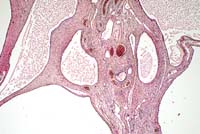

Contributor's Diagnosis and Comments: Cystic rete ovarii.

Multiple cysts of variable diameter (up to 2 cm) displacing the ovarian parenchyma are visible. The cyst lining varies from single to several layers of flattened to cuboidal epithelium. Some of the cysts are lined by cuboidal ciliated epithelium. Several cysts are filled with proteinaceous fluid. Occasionally folds which protrude into the cyst lumen and contain a blood vessel in the apical part can be observed.

In cats, as in other mammals, the rete ovarii consists of three parts: an intraovarian rete system, a connecting rete system, and an extraovarian system. The intraovarian rete is located in the ovarian medulla and is lined by cuboidal epithelium. At the tubular extremity of the ovary, the intraovarian system becomes a reticular formation of dilated tubules lined by ciliated columnar epithelium- the connecting rete. The extraovarian rete consists of tubules composed of ciliated columnar cells extending from the connecting rete and ending blindly in the periovarian tissue. Cysts of the rete system have been described in different species including cats. The epithelial lining of the cyst walls can vary from single to several layers of cuboidal or flattened to columnar and ciliated epithelial cells.

Conference Note: Cysts of the ovarian rete are only one of sixteen different types of cysts occurring in and around the ovary of domestic animals.3 The incidence and relative significance of these is variable among animal species. In the cow and sow, follicular cysts are most frequent, and are important causes of infertility. These occur less frequently in the bitch and queen. Cats with follicular cysts may show signs of hyperestrogenism. On the other hand, cystic rete ovarii are most common in the bitch and queen, and seldom if ever cause clinical signs.

Histologic differentiation of the various types of cysts can

be difficult. Important features include the type(s) of epithelium

lining the cyst, presence or absence of smooth muscle in the wall

of the cyst, and anatomic location.